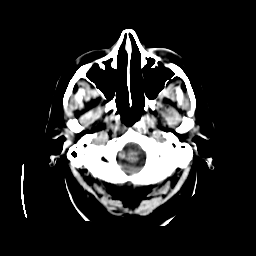

CT Study #2 -- Slice #2